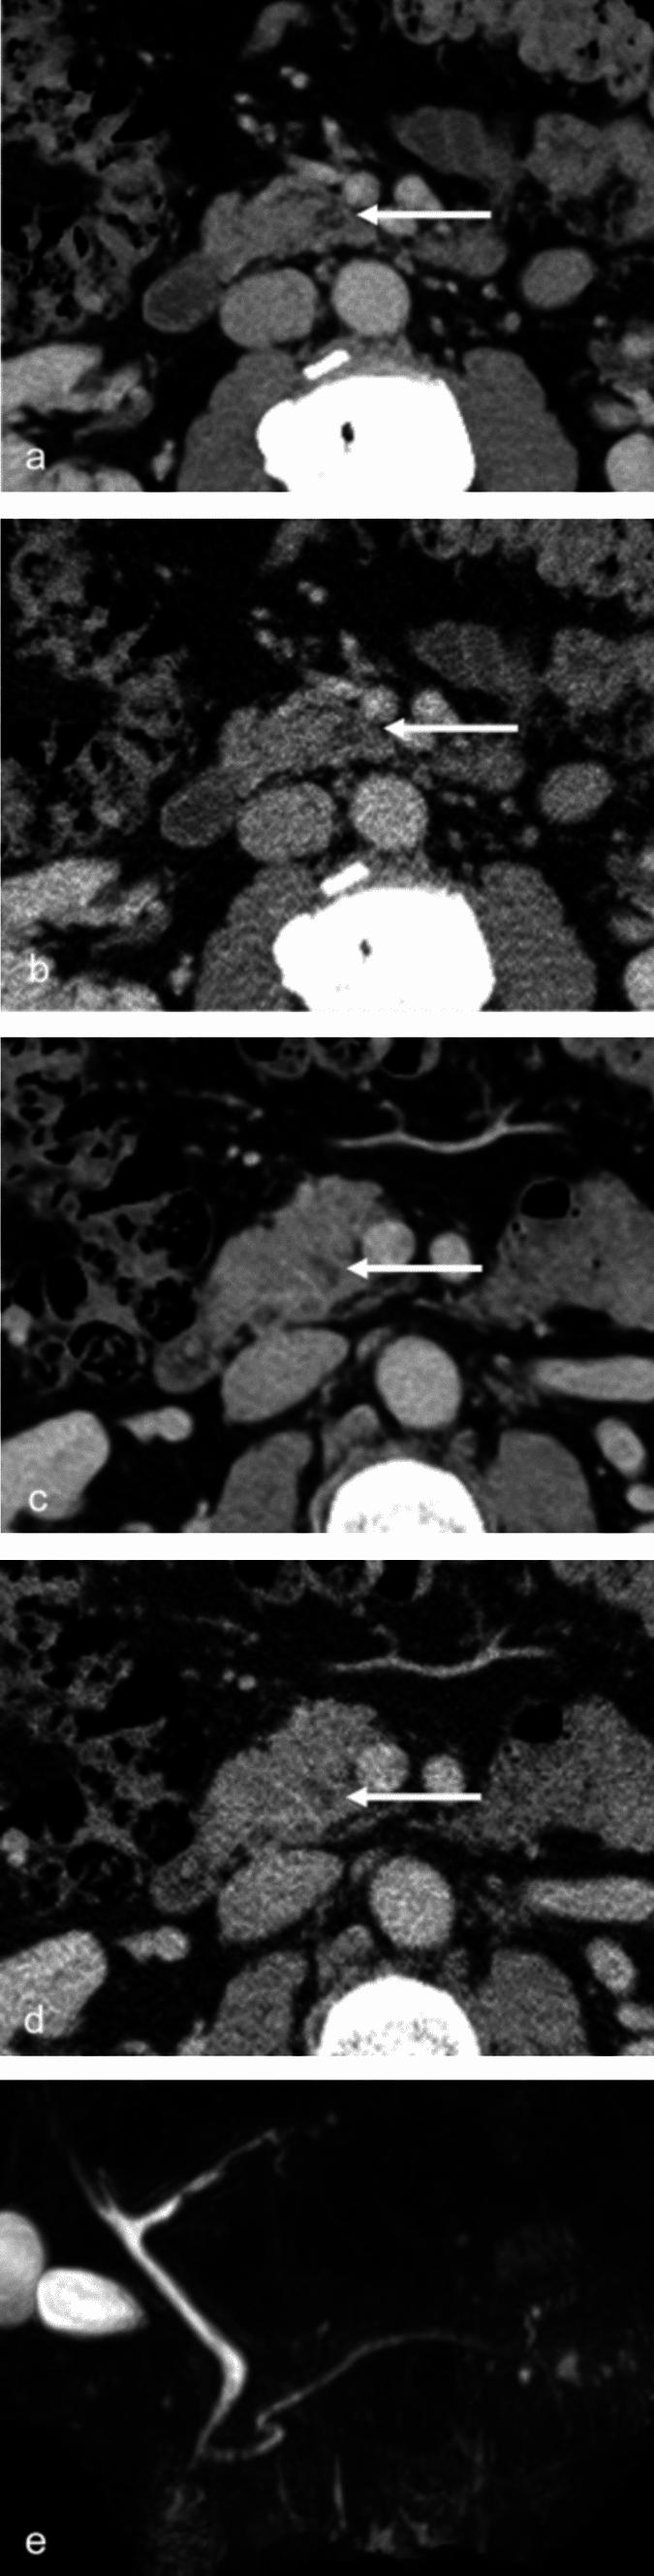

This study aimed to compare the image quality and detection performance of pancreatic cystic lesions between computed tomography (CT) images reconstructed by deep learning reconstruction (DLR) and filtered back projection (FBP). This retrospective study included 54 patients (mean age: 67.7 ± 13.1) who underwent contrast-enhanced CT from May 2023 to August 2023. Among eligible patients, 30 and 24 were positive and negative for pancreatic cystic lesions, respectively. DLR and FBP were used to reconstruct portal venous phase images. Objective image quality analyses calculated quantitative image noise, signal-to-noise ratio (SNR), and contrast-to-noise ratio (CNR) using regions of interest on the abdominal aorta, pancreatic lesion, and pancreatic parenchyma. Three blinded radiologists performed subjective image quality assessment and lesion detection tests. Lesion depiction, normal structure illustration, subjective image noise, and overall image quality were utilized as subjective image quality indicators. DLR significantly reduced quantitative image noise compared with FBP (p < 0.001). SNR and CNR were significantly improved in DLR compared with FBP (p < 0.001). Three radiologists rated significantly higher scores for DLR in all subjective image quality indicators (p ≤ 0.029). Performance of DLR and FBP were comparable in lesion detection, with no statistically significant differences in the area under the receiver operating characteristic curve, sensitivity, specificity and accuracy. DLR reduced image noise and improved image quality with a clearer depiction of pancreatic structures. These improvements may have a positive effect on evaluating pancreatic cystic lesions, which can contribute to appropriate management of these lesions.

本研究旨在比较深度学习重建(DLR)和滤波反投影(FBP)重建的 CT 图像对胰腺囊性病变的图像质量和检出性能。本回顾性研究纳入 2023 年 5 月至 2023 年 8 月期间行增强 CT 检查的 54 例患者(平均年龄:67.7±13.1 岁)。在符合条件的患者中,胰腺囊性病变阳性和阴性患者分别为 30 例和 24 例。采用 DLR 和 FBP 对门静脉期图像进行重建。使用腹部主动脉、胰腺病变和胰腺实质的感兴趣区计算客观图像质量分析的定量图像噪声、信噪比(SNR)和对比噪声比(CNR)。三位盲法放射科医师进行主观图像质量评估和病变检出测试。病变描绘、正常结构显示、主观图像噪声和整体图像质量作为主观图像质量指标。与 FBP 相比,DLR 显著降低了定量图像噪声(p<0.001)。与 FBP 相比,DLR 显著提高了 SNR 和 CNR(p<0.001)。三位放射科医师在所有主观图像质量指标中均对 DLR 给予了更高的评分(p≤0.029)。DLR 和 FBP 在病变检出方面的性能相当,受试者工作特征曲线下面积、敏感性、特异性和准确性均无统计学差异。DLR 降低了图像噪声,提高了图像质量,使胰腺结构的显示更加清晰。这些改进可能对评估胰腺囊性病变产生积极影响,有助于对这些病变进行适当的管理。